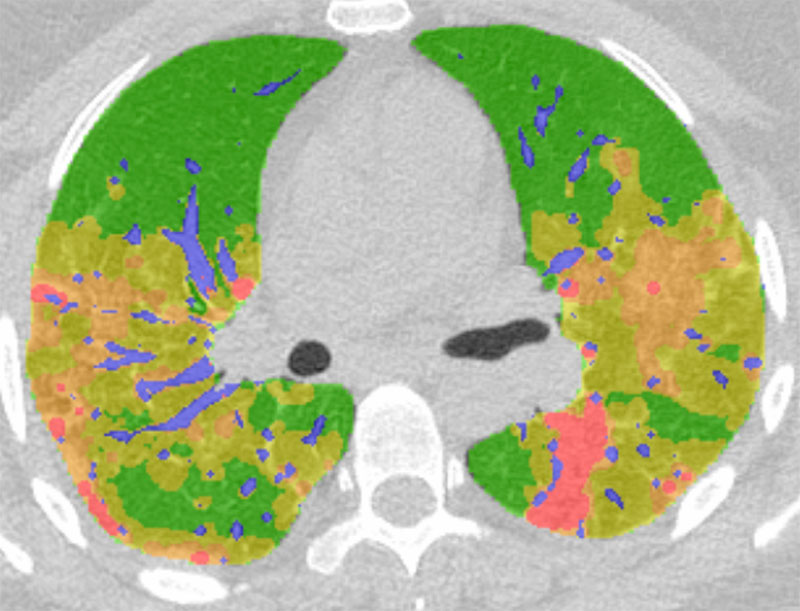

Легкие при Covid-19 . Фото: rsna .org . Одним из долгосрочных последствий коронавируса может быть фиброз легких - затвердение легочной ткани, после чего орган не может нормально функционировать .

Поражение легких при коронавирусе подразделяется на 5 степеней, которые определяются в процентном соотношении к здоровым тканям . Процент воспалительного процесса высчитывается . . .

К чему приводит воспаление легочной ткани, какие последствия у фиброзов, необратимые процессы в альвеолах при covid-19, все про поражение легких при коронавирусе .